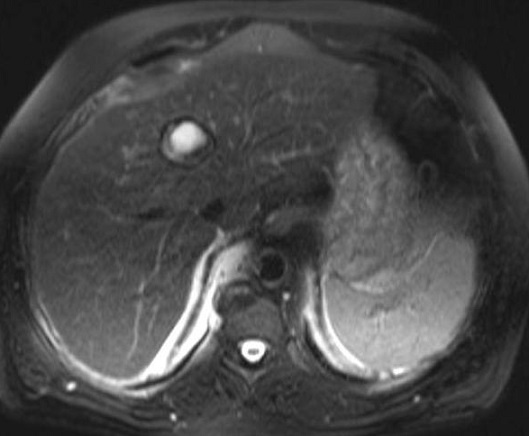

|

Meme cas en ponderation T2 ,

coupe axiale : La lesion est tres hypersignale et sa

paroi se retrouve en hyposignale tres nette |

Image d'une kyste hydatique avec des

vesicules de filles hypersignal au sein des kyste

avec image de pleuresie par rupture du kyste dans la

plevre du poumon droit . Coupe axiale IRM ponderer

sur T2 |